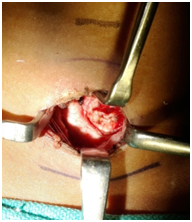

Figure 3 Intra-operative picture of the patient.

During tracheostomy, incidentally an unusually high Innominate artery was encountered over trachea in midline traversing laterally to the right side of the neck at the level of third tracheal ring. Through per oral approach the tongue mass was lifted from the underlying muscles in a plane using coblation and bipolar cautery and was excised in to with a margin of 5mm all around including at depth. Post operative period was uneventful. The patient was decannulated on day two and the oral feeds were started on day two only. The patient was discharged on post operative day three.